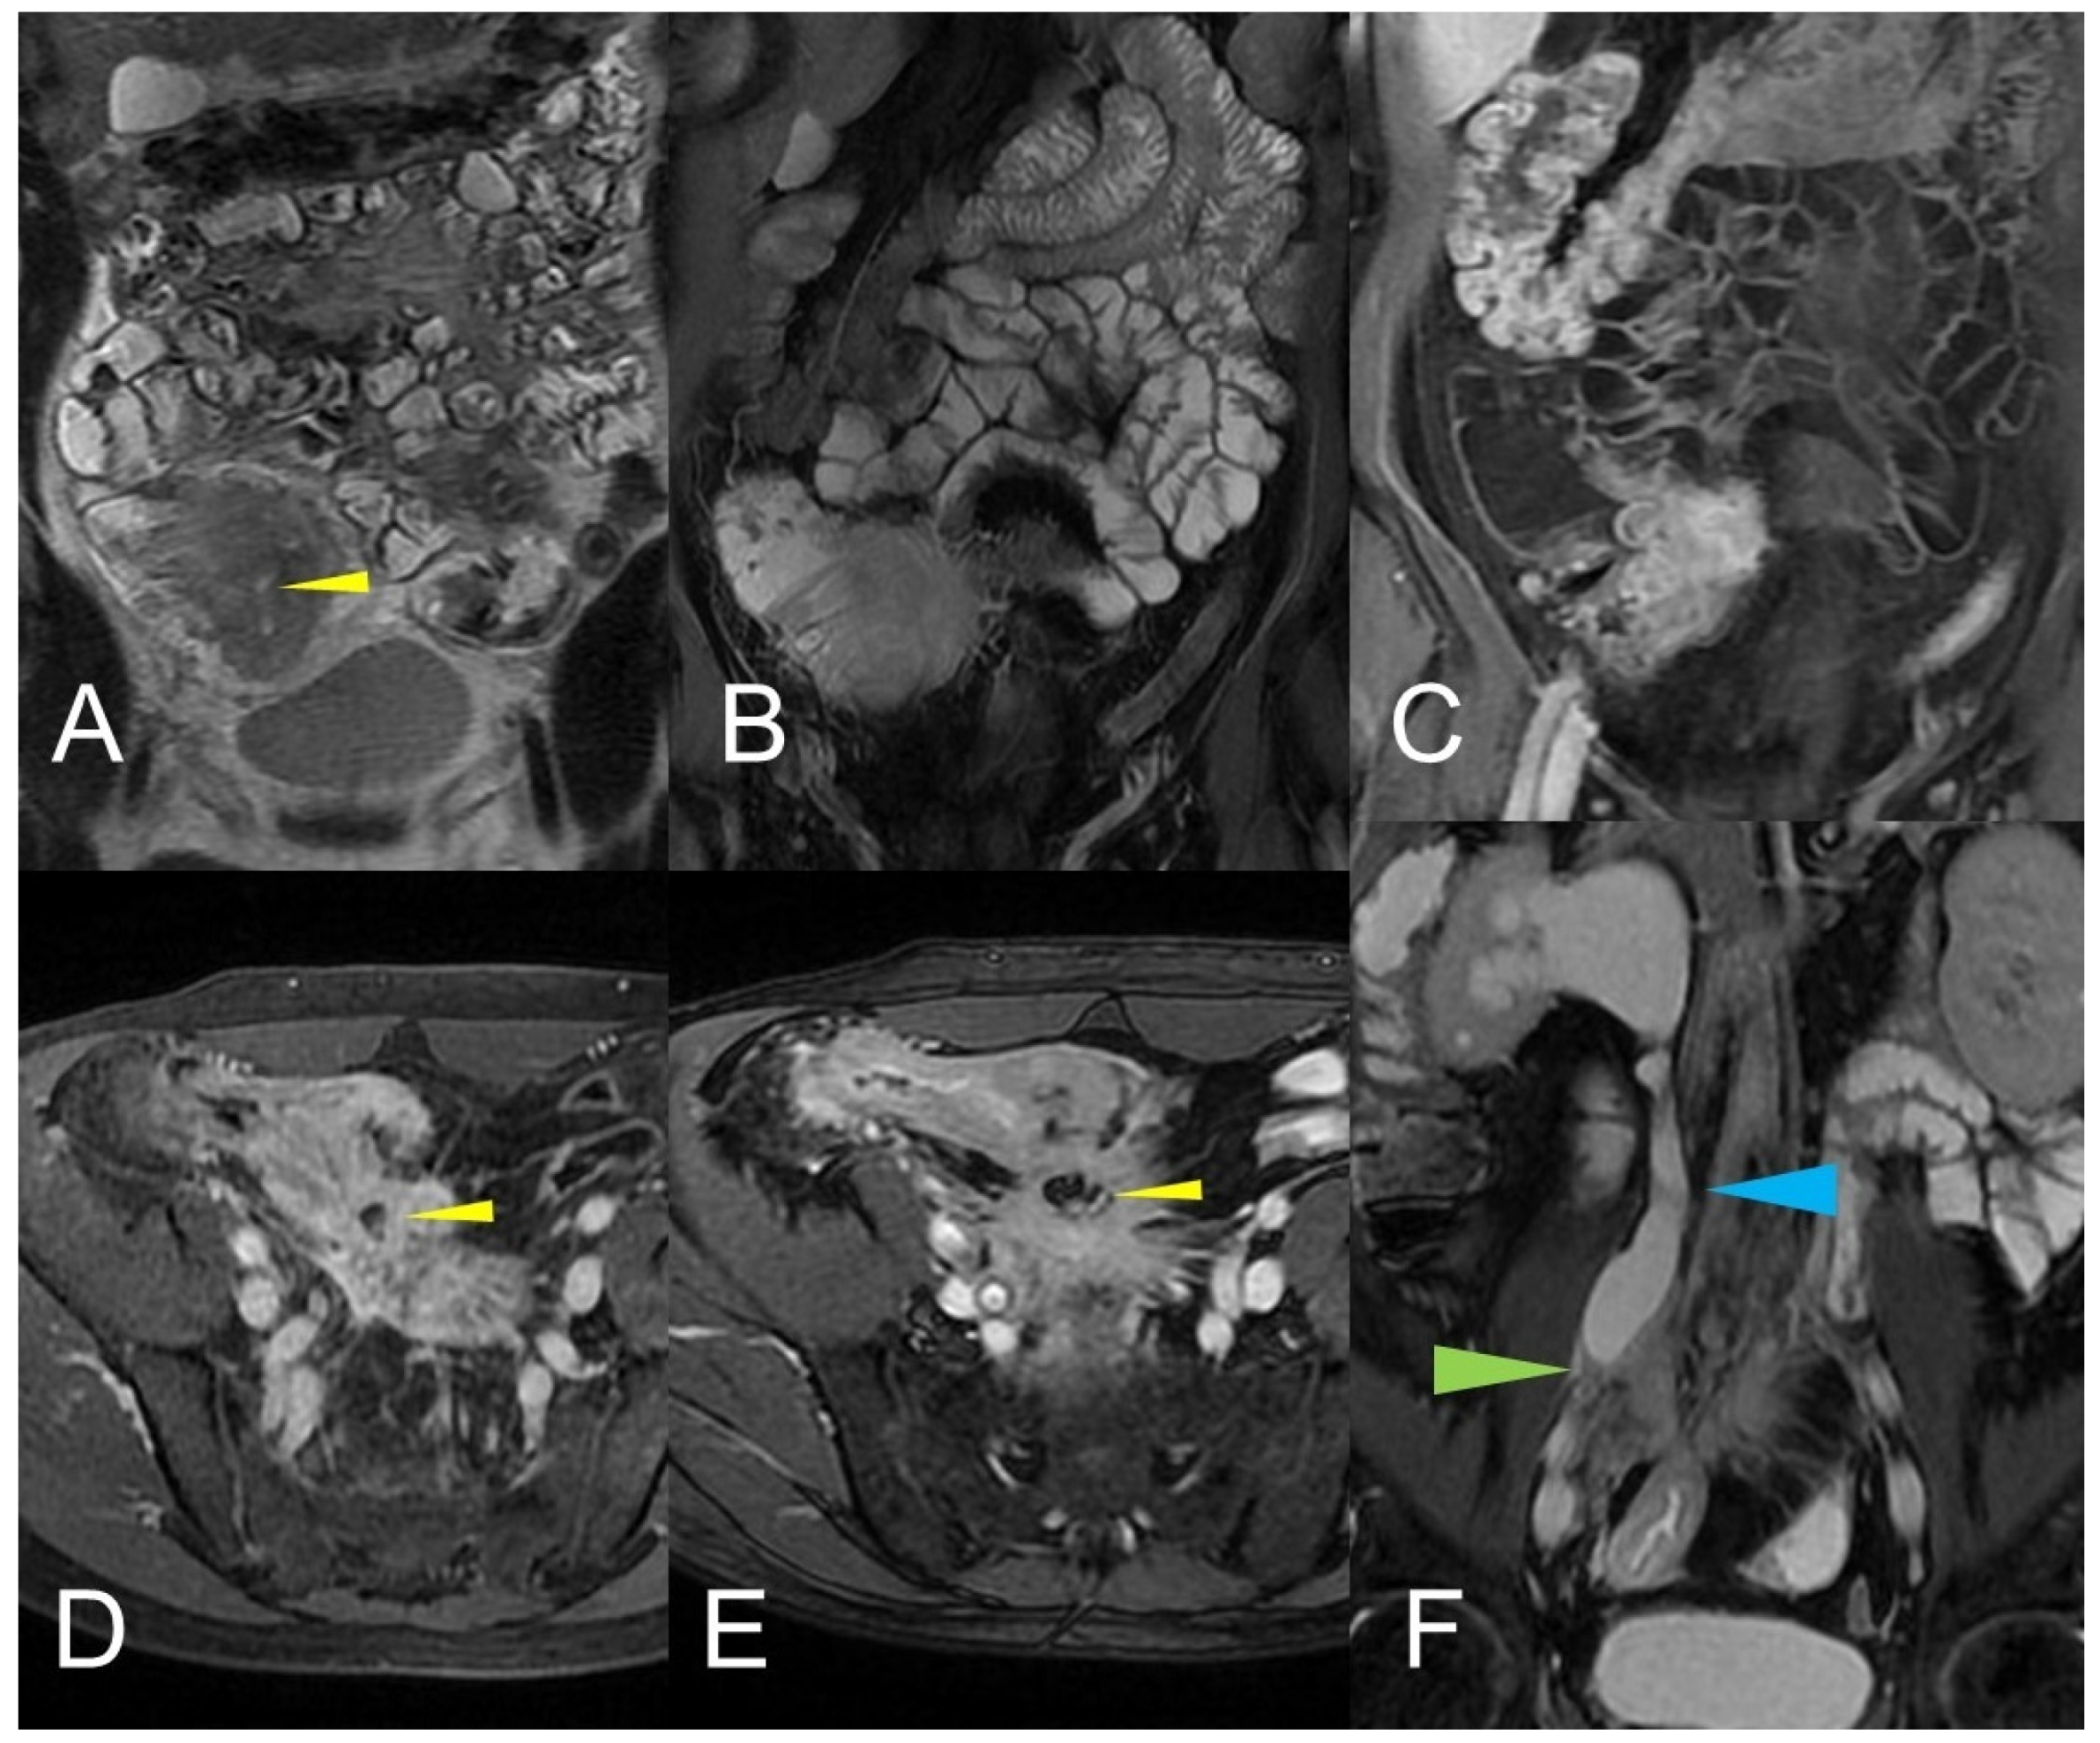

Figure 12.

Inflammatory conglomerate represents a climbing mesenteric fat involvement in the context of penetrating disease and mesenteric inflammation. The components of the fistulas within the mass can be difficult to detect because it often coexists with phenomena of retraction that are expressed on the intestinal loops nearby or on the ureters. Small inflammatory conglomerate in the context of the mesentery adherent to a segment of the pathological small intestine, with active disease (yellow arrowheads in (A,C): coronal (A) and axial (C) contrast-enhanced fat-suppressed T1-weighted image and in (B,E) (coronal fast imaging employing steady-state acquisition; FIESTA image) and (D) (coronal T2-weighted MRE image)).

Figure 13.

Two different patients with, respectively, an inflammatory conglomerate (Patient 1) of medium size (yellow arrowheads in (A–C)) and of large size (green arrowheads in (D–F)) (Patient 2). Coronal (A,B) and axial (C) fast imaging employing steady-state acquisition (FIESTA) image. Coronal FIESTA image (D) and coronal without (E) and with (F) contrast-enhanced fat-suppressed T1-weighted image. Notably intense contrast enhancement in (F) image underlines the significant state of inflammation of the disease in the active and complicated phase.

Figure 14.

Large climbing inflammatory conglomerate. A small abscess is evident in the center of the inflammatory conglomerate (yellow arrowheads in (A,D,E)). It shows marked enhancement (yellow arrowhead in (C)) and determines conspicuous retracting effects both on the mesentery (spiculate aspect in (D,E)), in which it develops, and on the adjacent loops. In this patient, the right distal pelvic ureter is also narrowed, (green arrowhead in (F)) with hydronephrosis (blue arrowhead in (F)). (A): coronal T2-weighted MRE image; (B,F): coronal fast imaging employing steady-state acquisition (FIESTA) image; (C): coronal contrast-enhanced fat-suppressed T1-weighted image; (D,E): axial contrast-enhanced fat-suppressed T1-weighted image.